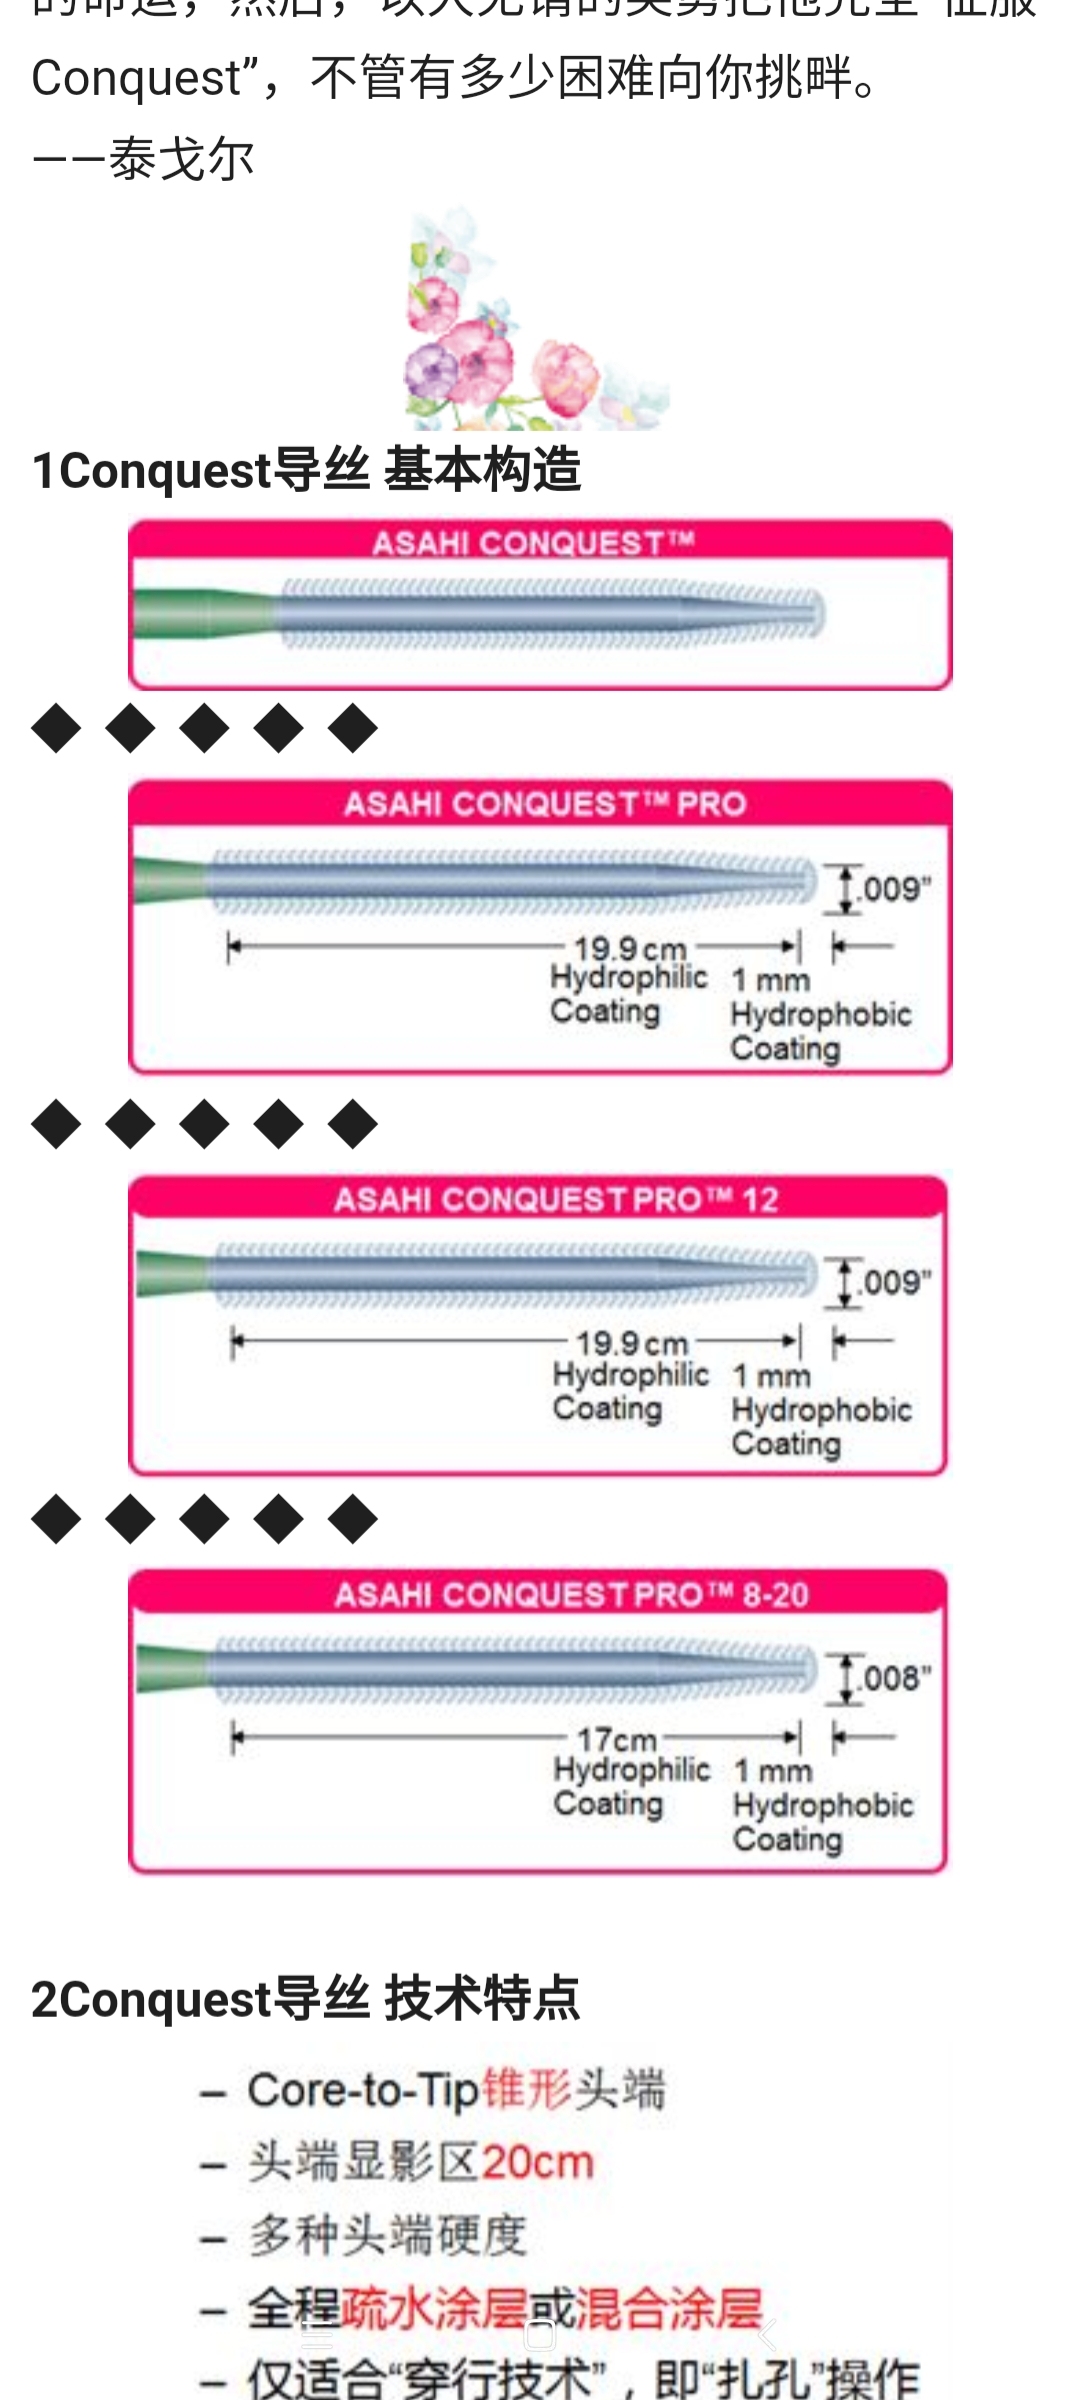

备好心心念的Conquest Pro 8-20,准备开干